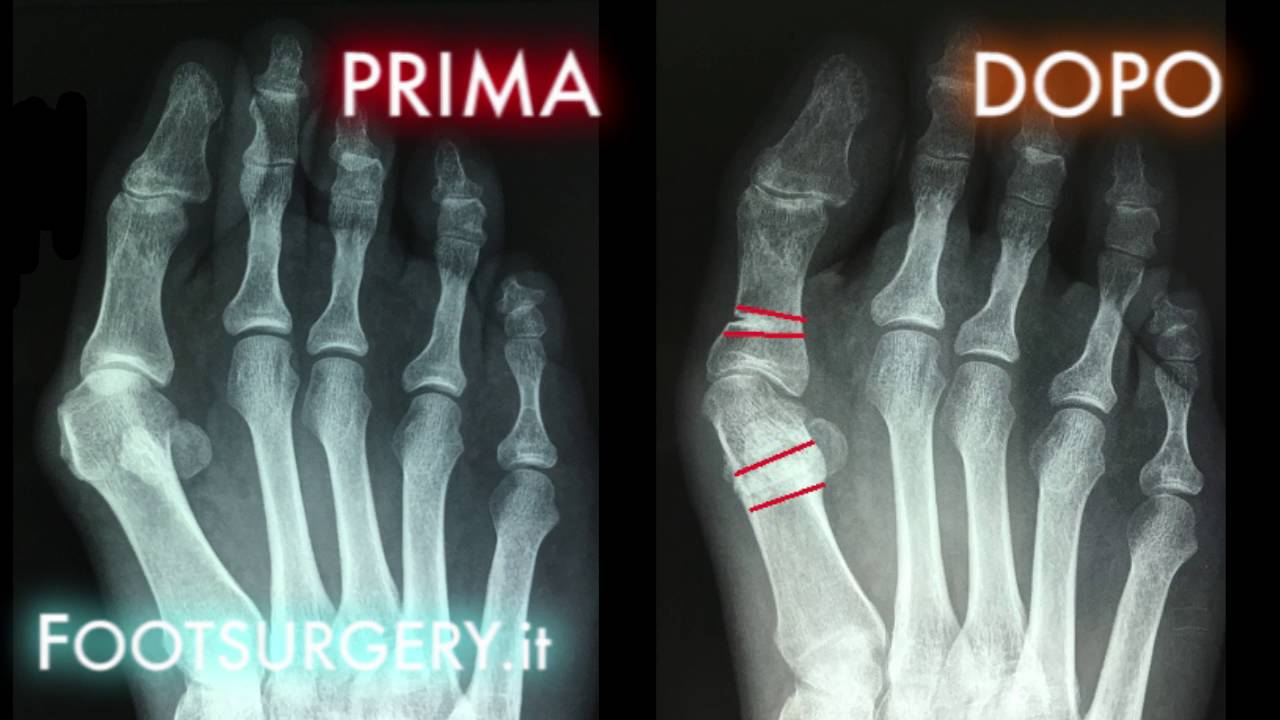

Ultimi ALLUCE VALGO: L'INTERVENTO CORRETTO | Alluce valgo prima e dopo | Dott. Andrea Scala

L'alluce valgo: cos'è, gli errori che vengono commessi nell'intervento e qual è invece la corretta procedura. Scoprilo in questo interessante video e contattaci per informazioni o per prenotare una visita con il Dott. Scala.